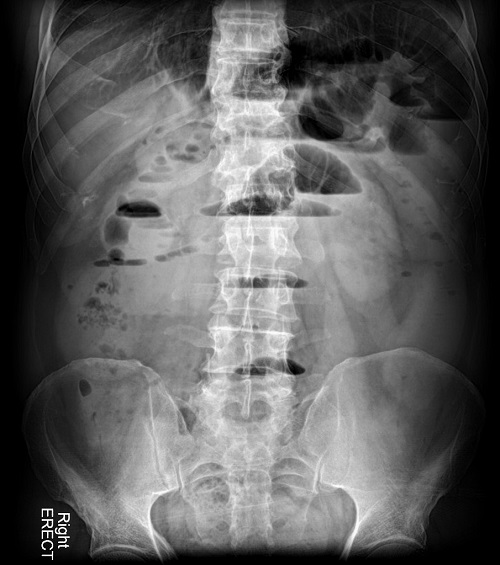

- Gold Standard: Abdominal X-Ray

Upright chest x-ray, upright and supine abdominal radiographs are all obtained. If patient cannot stand, they will lay on their side to visualize the air-fluid levels on x-ray. Findings on positive SBO include:

- Dilated bowel loops WITH air-fluid levels: when upright or lateral, the radiograph can visualize the interface between the air and fluid, as the content settles down and cannot move through.

- Average air-fluid level width of 2.5cm or more may indicated severe or complete obstruction.

- If air-fluid levels differ by more than 5mm in the same loop on upright film, this may indicate a mechanical cause.

- “A string of pearls” sign may be seen, if the loops are completely full with no air.